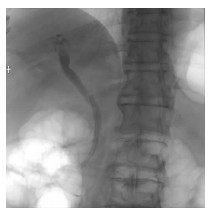

肝病超声诊断指南

中华医学会超声医学分会, 中国研究型医院学会肿瘤介入专业委员会, 国家卫生和健康委员会能力建设和继续教育中心超声医学专家委员会

2021, 37(8): 1770-1785. DOI: 10.3969/j.issn.1001-5256.2021.08.007

摘要(3068) HTML (6587) PDF (9311KB)(804)

超声检查无创、实时、价廉,无辐射、便于反复进行,是最常用的肝脏影像学检查方法。近年来,超声检查新技术如超声造影、弹性成像发展迅速,可有效鉴别肝内占位性病变性质、评估肝纤维化和门静脉高压程度以及监测肝病治疗效果,在临床肝病及其介入治疗中发挥重要诊断价值。本指南规范了肝病多模态超声技术(灰阶超声、彩色多普勒超声、超声造影、弹性超声)检查的仪器调置、患者准备及医生检查方法;对肝脏弥漫性病变(炎性病变、纤维化、硬化)、多种占位性病变及肝病介入操作的多模态超声技术诊断标准进行了定义和规范,同时推荐了超声监测周期及肝脏疾病超声诊断报告书写规范。